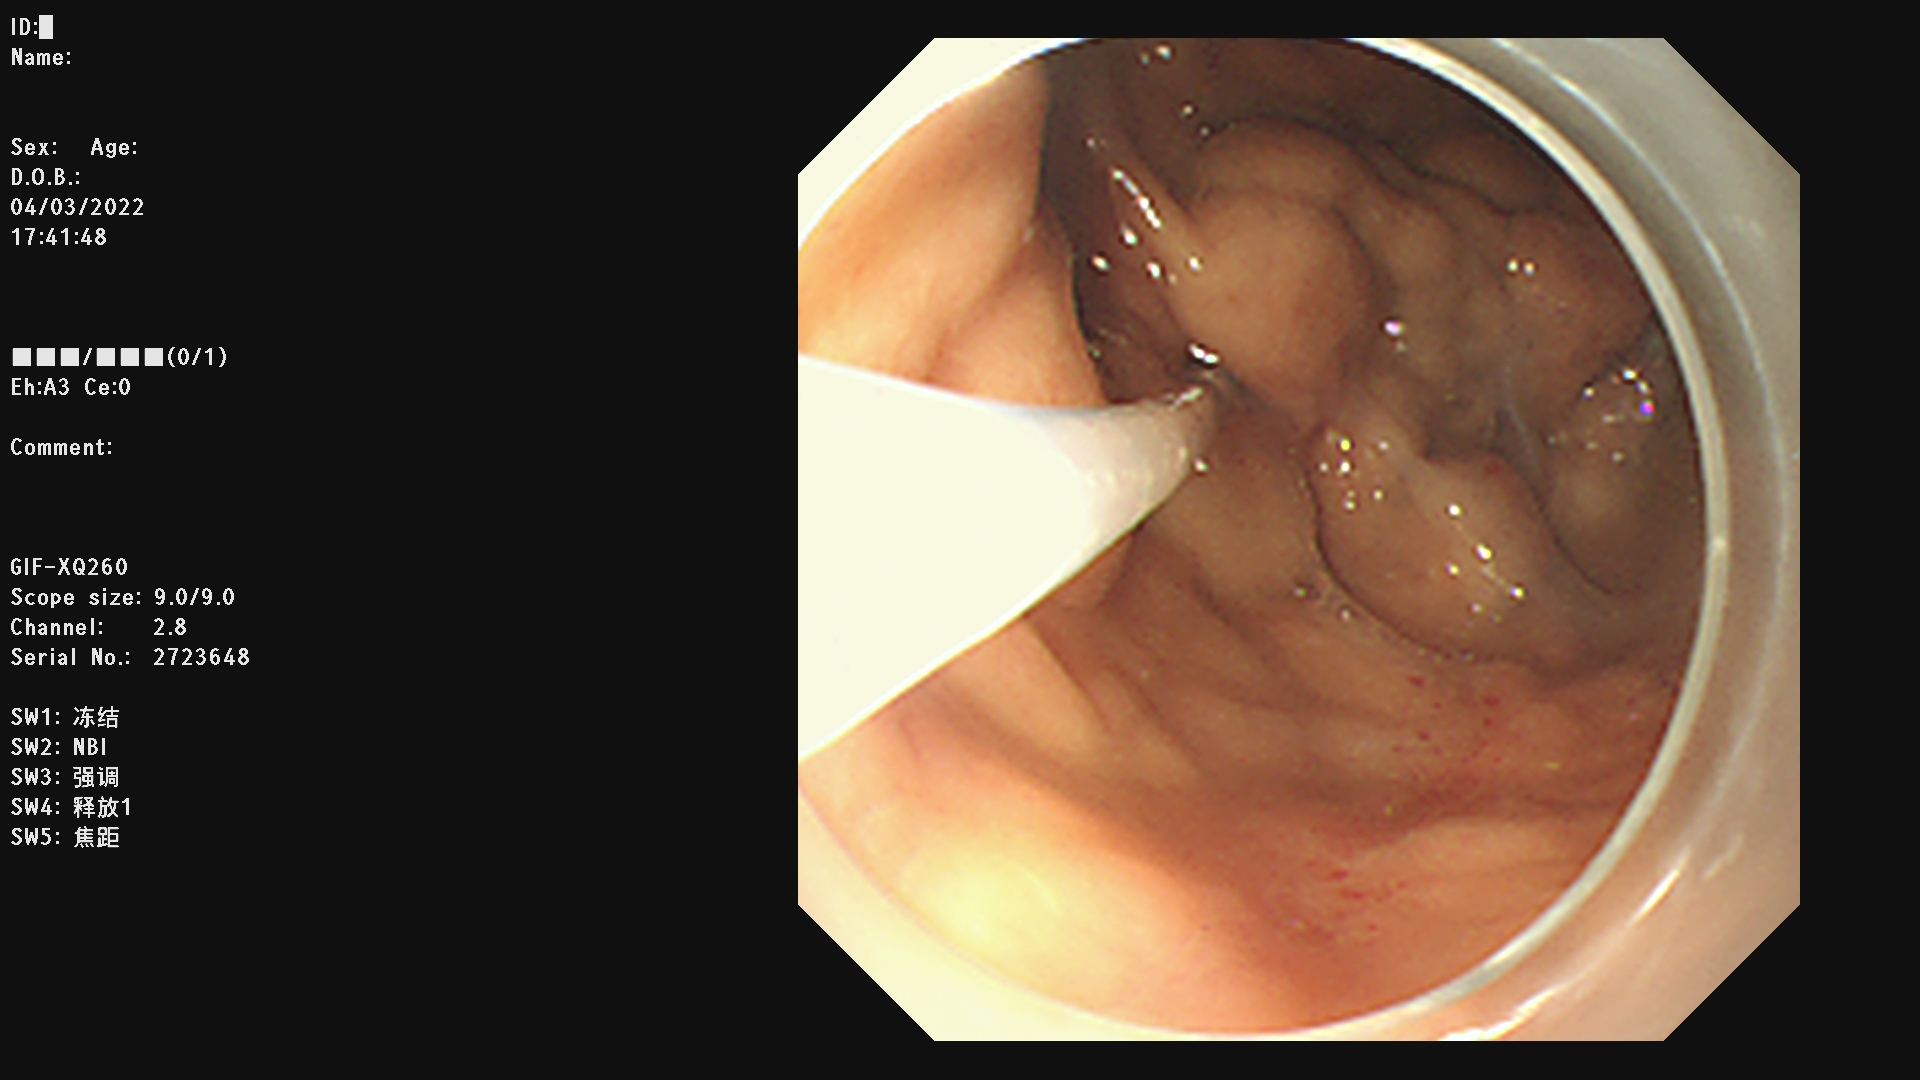

例一 :